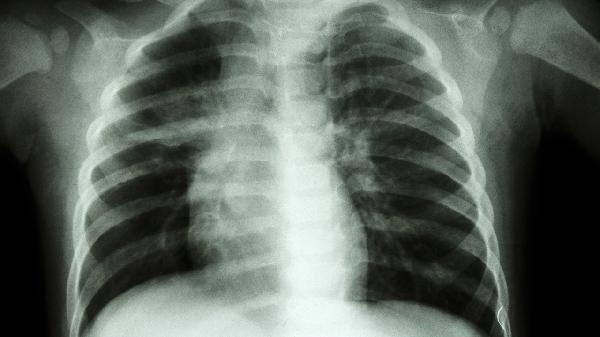

持续5年以上接触二氧化硅粉尘的工人,肺部病变概率明显上升。矽肺潜伏期可达10-20年,早期表现为咳嗽胸闷,后期出现进行性肺纤维化。建议接触史超3年者每年进行高分辨率CT检查,确诊后应立即终止粉尘接触。